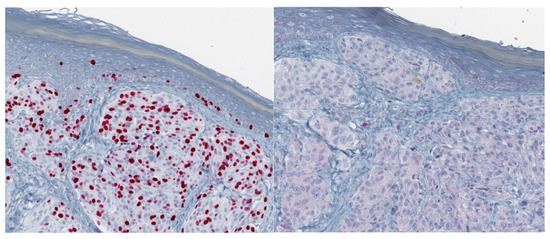

Figure 3.

43-year-old female, abdomen–Spitz melanoma; upper row: asymmetric melanocytic proliferation composed of enlarged, nodular or sheet-like aggregates of melanocytes and diminished maturation; spindle and epithelioid melanocytes show nuclear enlargement, pleomorphism, thickening and irregularity of nuclear membranes and prominent nucleoli; lower row: high proliferative activity by Ki-67/MIB-1 (left) and loss of p16 by immunohistochemistry (right).